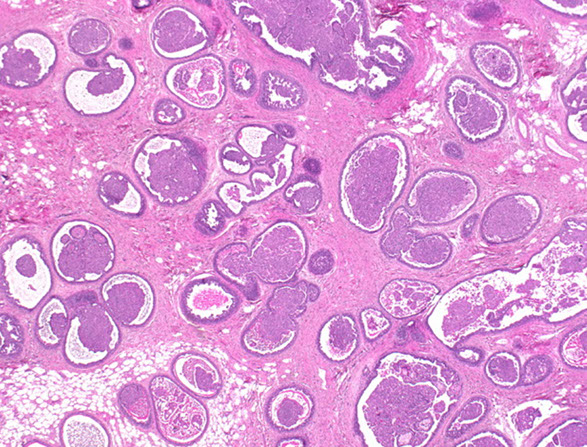

Phyllodes tumor (PT)

-ie cystosarcoma phyllodes

rare (<1%), biphasic lesion

occur in older age than FA (usually in 40s);

- may be derived from FA's

Clinically see rapidly enlarging mass; higher incidence in Latino women and Asian Americans

Larger than FA (4-5 cm)

- the larger the lesion, and presence of necrosis the higher likelihood of malig

Grossly, multinodular circumscribed masses of whorled gray tissue

- may see clefts, cysts and cauliflower like appearance

Histo: Periductal stromal hypercellularity (and periductal stromal heterogeneity, having areas with more hypercellular stroma and areas with more hypocellular stroma) and prominent intracanalicular growth pattern

- Maple-leaf appearance from stroma juttin into cystic spaces

- UDH common

Malig potentional based on stromal cellularity, stromal atypia, stromal mits, tumor margin, stromal overgrowth (one 4x field of pure stroma, no epithelium) - all are subjective

The epithelium is polyclonal and the stoma is clonal (vs most other fibroadenomas)

Recurrence more likely in malig lesions; usually are more atypical

Mets uncommon (up to 1/4 in malig lesions), but usually are composed of stroma that goes to lungs and bones

IHC: (+) stromal CD34, nuclear B-catenin, ER

- neg: CK903, SMA, desmin

- Ki-67, p53, and CD117 (c-kit) predicative of malig (c-kit of recurrency)

Call fibroepithelial lesion c inc stromal cellularity if uncertain of PT, but to get more breast tissue excised

DDx: Cellular FA / juvenile / PASHy FA, sclerosing lobular hyperplasia

Tx: wide excision

- axLN eval not usually done (mets to axLN <1%)

- MC mets to bone and lung (up to 25% if malignant!)

-- more benign course when occurs in younger pts

Px: >70% Benign, although even b9 tumors can recur (up to 20%)

- benign PTs may be tough to differentiate from cellular FAs

- malignant PTs have high mits (>10 mits / 10 hpfs) and is highly pleomorphic; but mits in general aren't necessary to dx

-- malignant/borderline phenotype: +1q, +5p, +7, +8, -6, -9p, -10p, -13

-- malig PTs must be ddx'd from spindle cell carcinomas and primary breast sarcomas

- malignant PTs act more like sarcomas and tend to met to the lung instead of the LN (as in carcinomas)